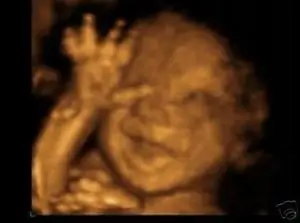

Hide and Go Seeker Этот драгоценный выглядит так, будто играет в игры в мамином животике. Теперь ты видишь меня, а теперь нет. Фото

такие возможны через такие места как

Peek a Boo 3D/4D Ультразвуковые студии.